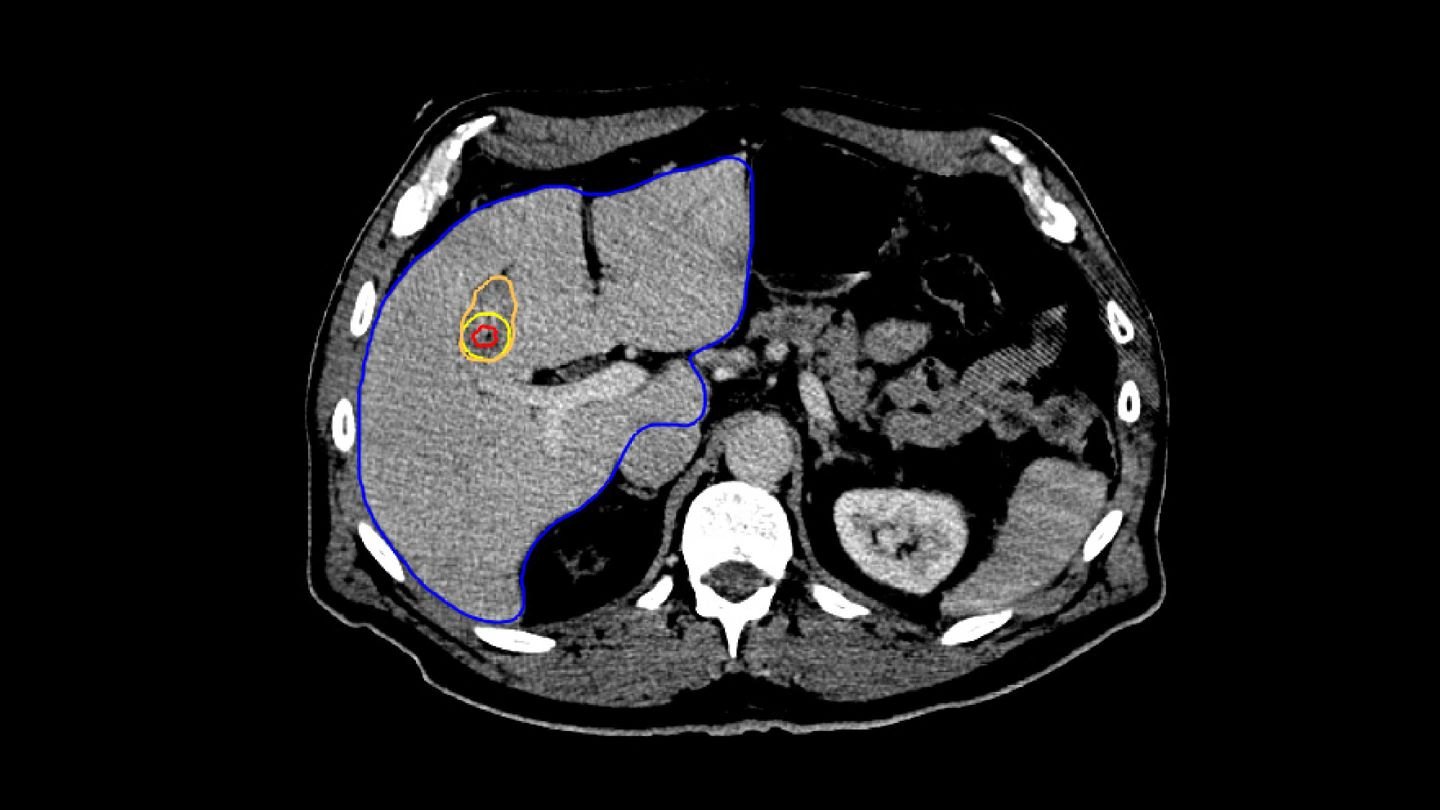

3. VERIFICATION

For treatment verification, both the minimal ablative margin calculation and visual inspection based on deformable mapped tumors are provided in the Liver Ablation module.

In Paulucci et al., it was shown that using biomechanical deformable registration, the local disease progression risk decreased to less than 1% with an intraprocedurally confirmed minimum ablative margin greater than 4.6 mm.